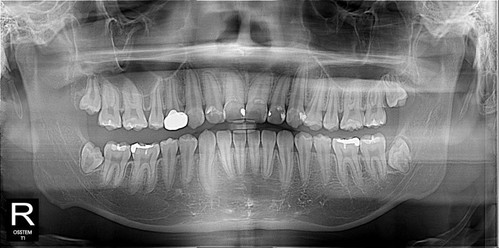

우측 구치부 교합이 좋지 않아 교정을 시작했고 교정을 하면서 치아이동을 위해 사랑니 발치를 해야했다...

좌측 매복정도가 깊어 한쪽씩 뽑아야한다고 얘기했지만